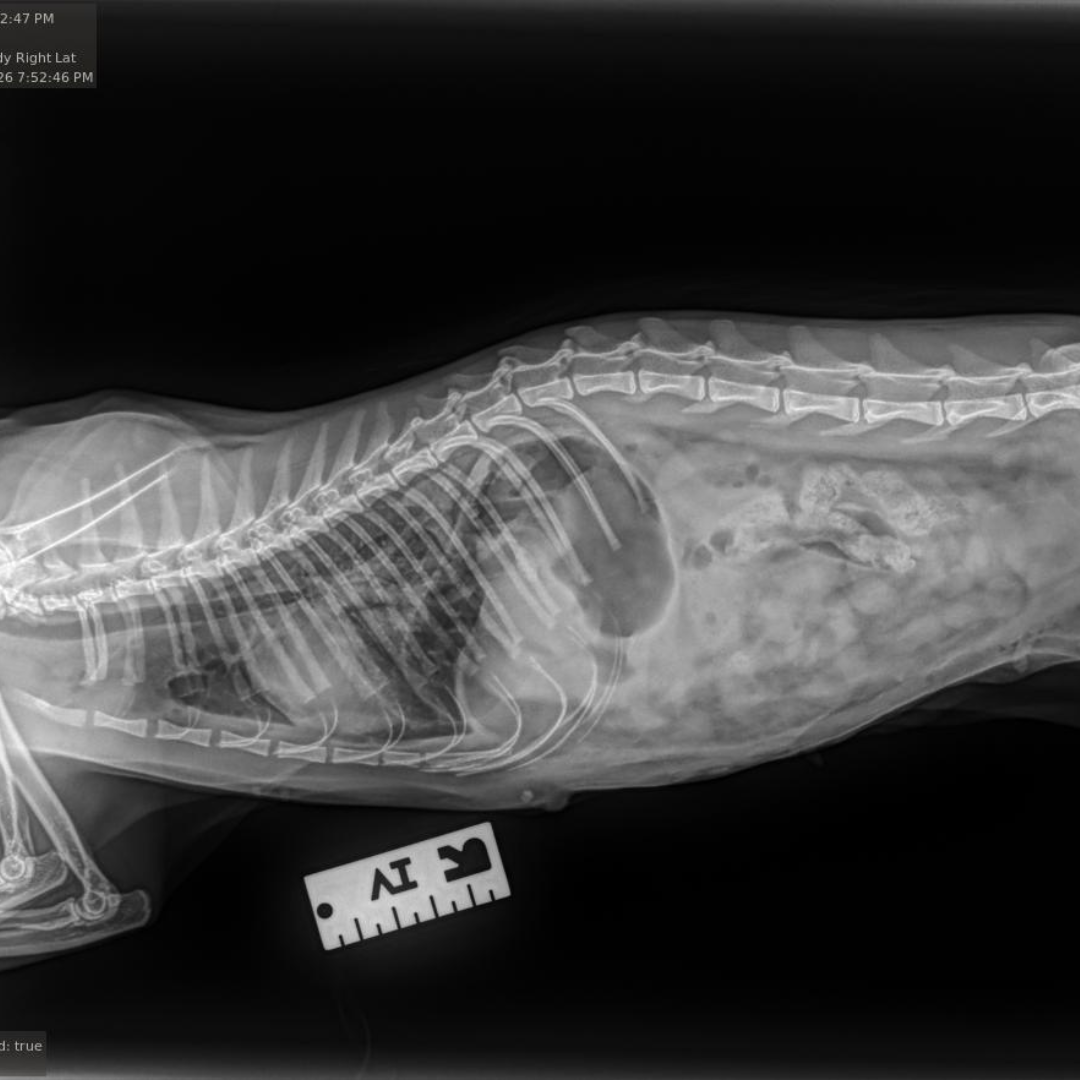

Our veterinary team at the Bredel Clinic acted quickly. Diagnostic X-rays revealed a diaphragmatic hernia, along with concern for a possible internal tumor or an enlarged kidney. A diaphragmatic hernia, as seen in the X-rays below, occurs when a rupture in the diaphragm allows abdominal organs, such as the liver, stomach, or intestines, to move into the chest cavity. This condition is most often caused by severe trauma, like being hit by a car or suffering a major fall, and it can lead to significant respiratory distress, rapid or shallow breathing, muffled heart and lung sounds, and chronic weight loss if left untreated.

During surgery, our veterinarians discovered that Raven’s kidney was severely enlarged, nearly double its normal size, and ultimately had to be removed. Additional scarring was found on her spleen, further confirming that she had likely suffered a significant traumatic injury in her past.